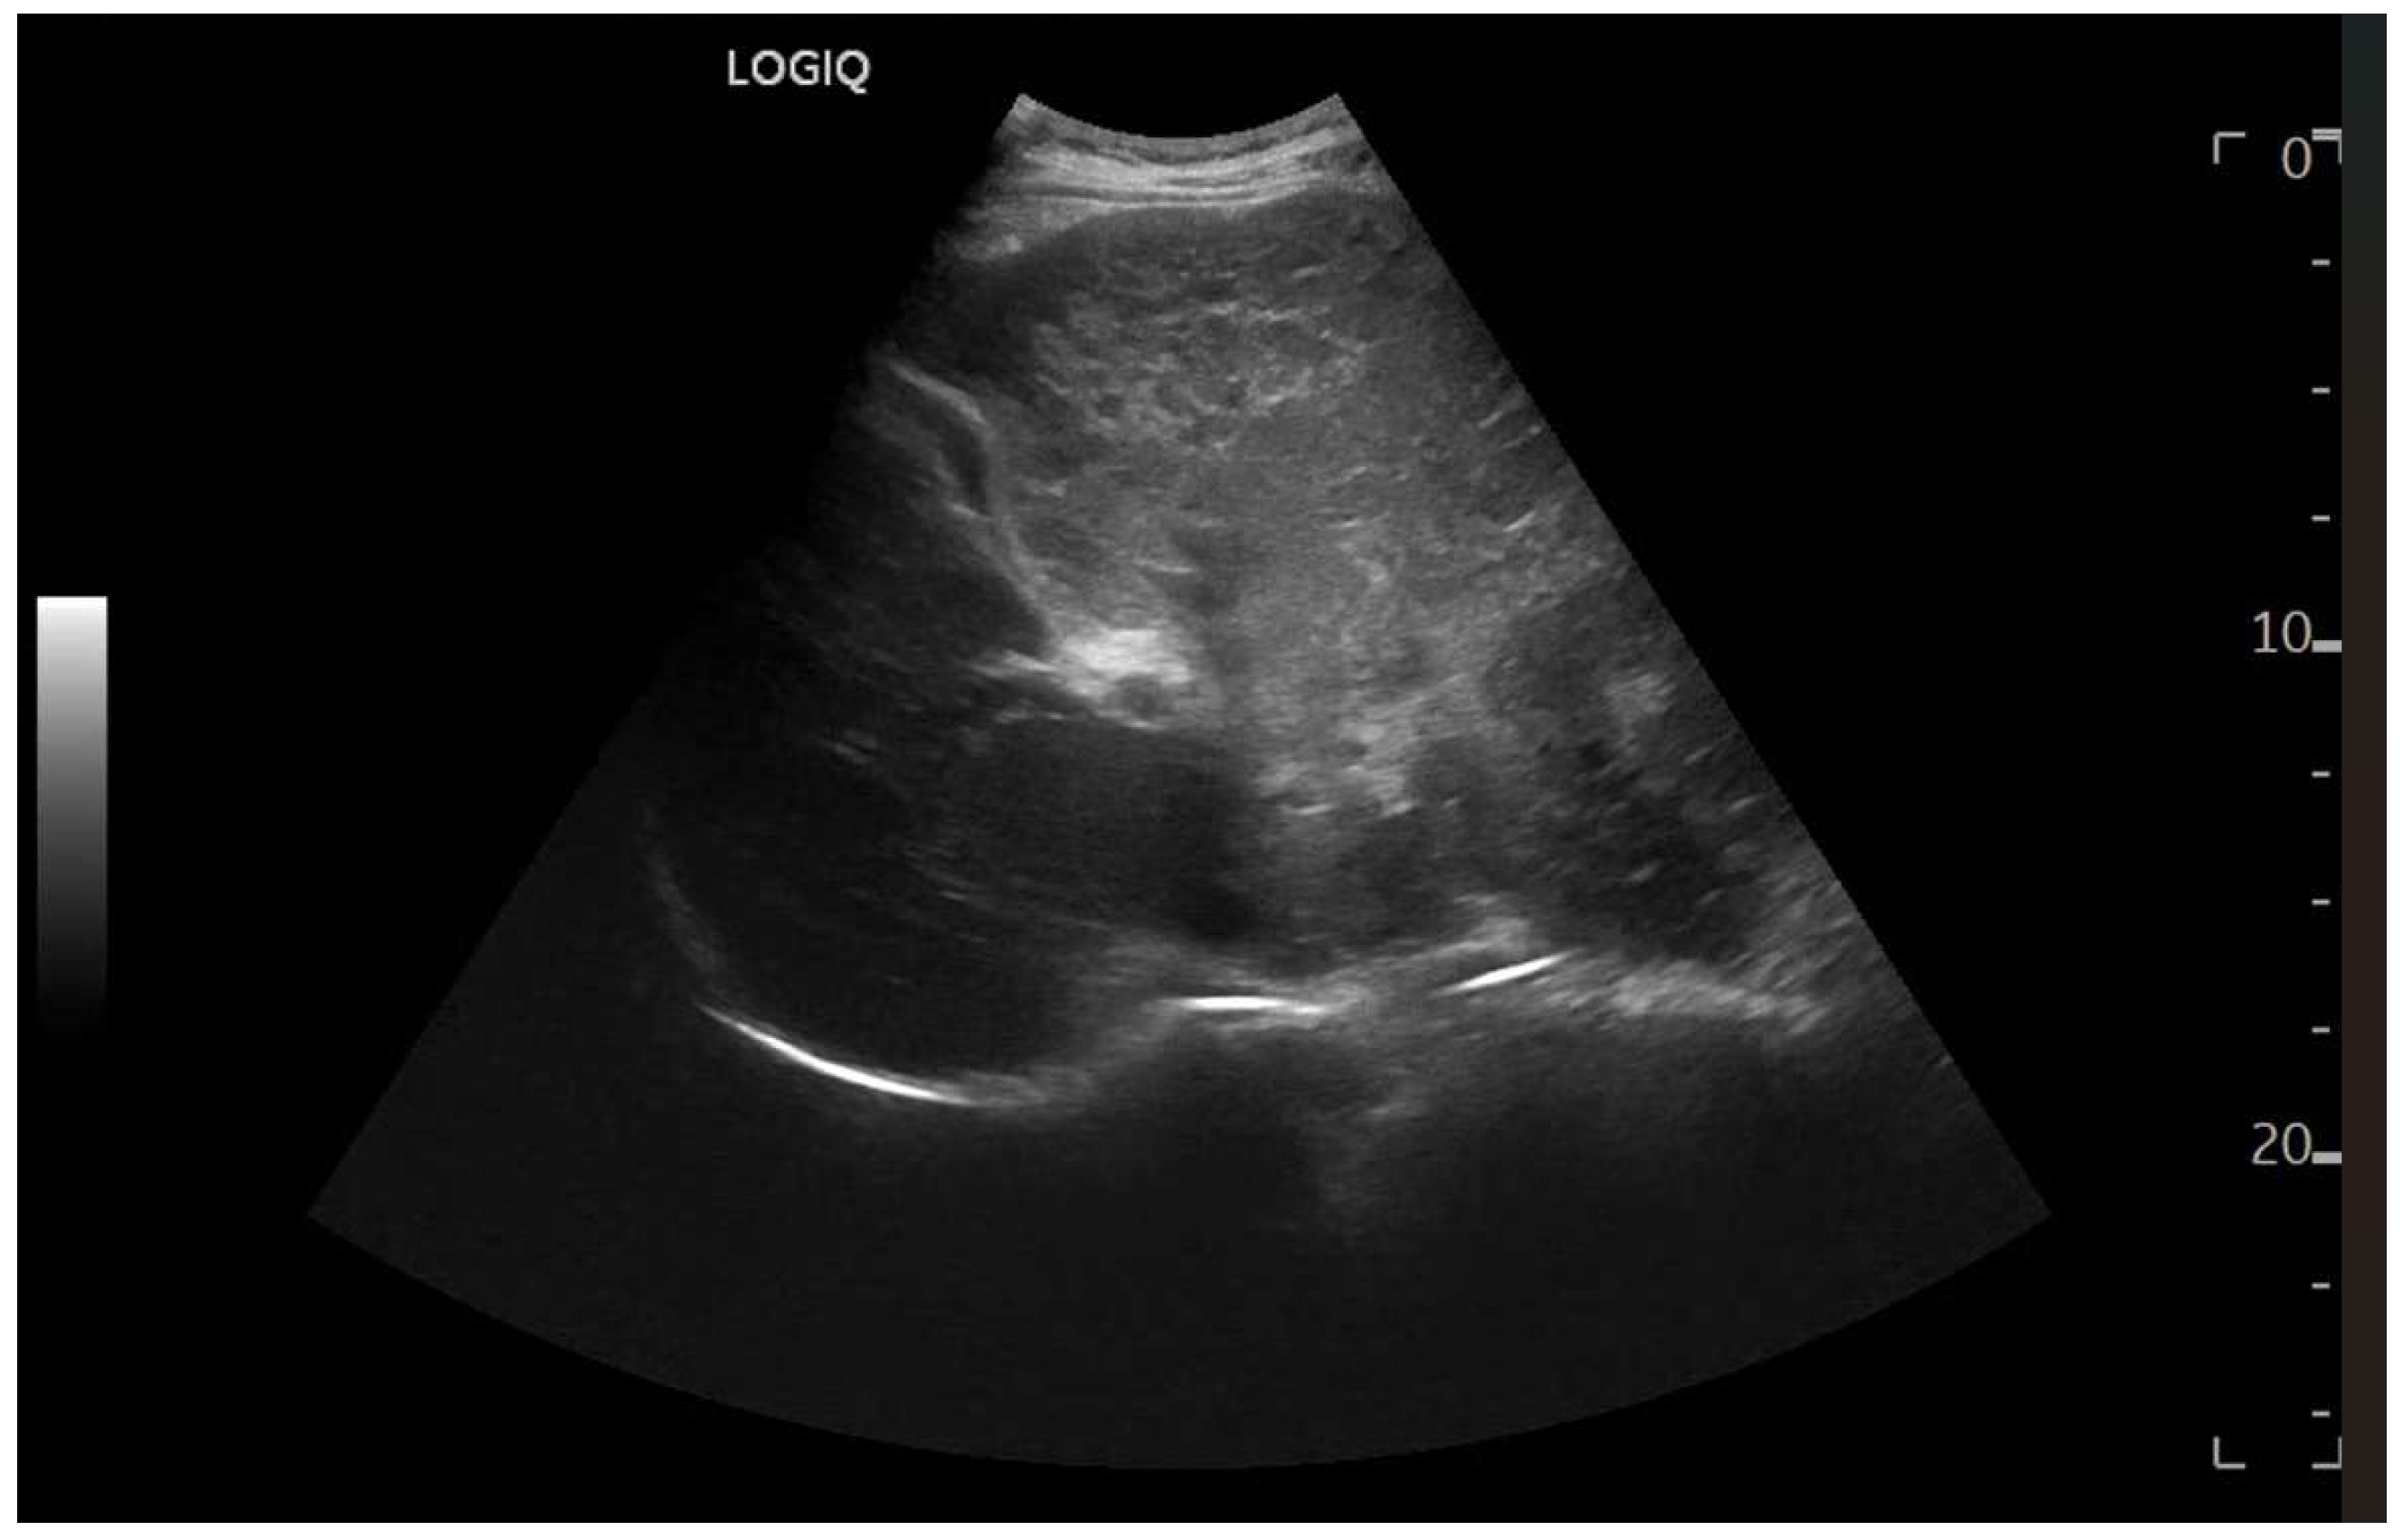

Figure 7.

Hypotrophy of the right lobe. Nodular profiles. Markedly heterogeneous echostructure, with increased fibrous component and fibrous trabeculae delimiting pseudo-nodular areas, within the context of a vascular-type cirrhosis.